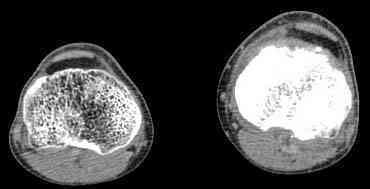

важаемые коллеги! Поступил больной 22 лет. Болен с января 2006 - появились боли в области верхнейтрети голени. При первичном осмотре в поликлинике был заподозрен первично-хронический остеомиелит - осмотрен гнойным хирургом - произведена биосия . Заключение - хондросаркома. Осмотрен онкологом - с учетом характера опухоли - химиотерапия, лучевое лечение не показано. Предложена либо ампутация, либо решение вопроса о возможности выполнения органосохраняющей операции. При обращении к нам произведена сцинтиграфия скелета - зоны гиперфиксации РФП: верхняя треть голени- 960%, нижняя треть бедра - 380%, Дистальный метафиз голени и затылочная область - 140%. В легких - метастазов нет. Произведена КТ (картинки в приложении). Учитывая абсолютную нестыковку рентгенологических и морфологических данных повторно биопсия. Выявлено, что первичная биопсия выполнялась из поверхностной параоссальной зоны - там локализованы хрящеподобные массы, далее очень плотная кость без хрящевых участков - биоптат взят фрезой с большим трудом. Морфологического заключения пока нет. Хотелось бы узнать Ваши варианты диагноза и соответственно тактику.